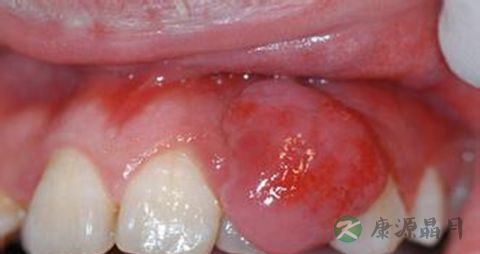

1、牙龈呈深红色或暗红色,肿胀肥大,龈缘圆钝,牙龈乳头呈球状。组织松软,探诊易出血,也可有脓性分泌物。严重者附着龈可因组织水肿,点彩消失,表面光亮,龈缘可有糜烂或肉芽增生,龈袋溢脓。急性牙周脓肿发病突然,牙龈红肿光亮,患处牙龈形成椭圆形或半球状的肿胀突起,未成熟时张力大,疼痛较明显,成熟后有波动感。患牙因牙周膜水肿而有“浮起感”,叩痛,松动明显。脓肿后期,脓液局限,脓肿表面较软,检查可见溢脓。可有局部淋巴结肿大,或有白细胞轻度增高。脓肿可自行破溃而消退。

2、若身体抵抗力降低时,可出现单发或多发性的龈脓肿,特别以龈乳头区较多见。若慢性牙周炎急性发作引起的牙周肿痛可伴牙齿松动。若是急性根尖周炎引起的牙龈肿痛可多可查及龋坏、隐裂等,并可有牙齿浮出感。牙龈肿痛患者多伴有牙龈出血、自觉牙龈发胀、口臭等。

引起牙龈肿痛的原因主要包括牙龈脓肿、牙周脓肿、智齿冠周炎或根尖周炎等,最为常见是牙周脓肿引起的病症,年轻人多见智齿冠周炎。

患者本身往往存在牙龈或牙周组织慢性炎症,当机体抵抗力下降,天气干燥,进食辛辣刺激的食物或患有全身系统性疾病,如糖尿病时,会导致原有慢性炎症急性发作,出现牙龈肿痛症状。